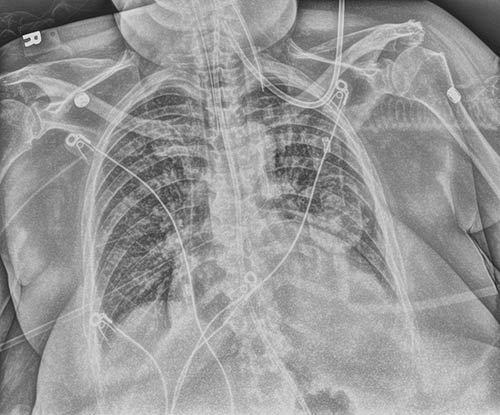

Be sure with a single exposure. Tube & Line Enhancement creates a companion image and uses optimized processing for clearer, easier visualization of PICC lines and tubes. It increases confidence that tubes and lines are placed correctly – and remain in position.

Modified

Original